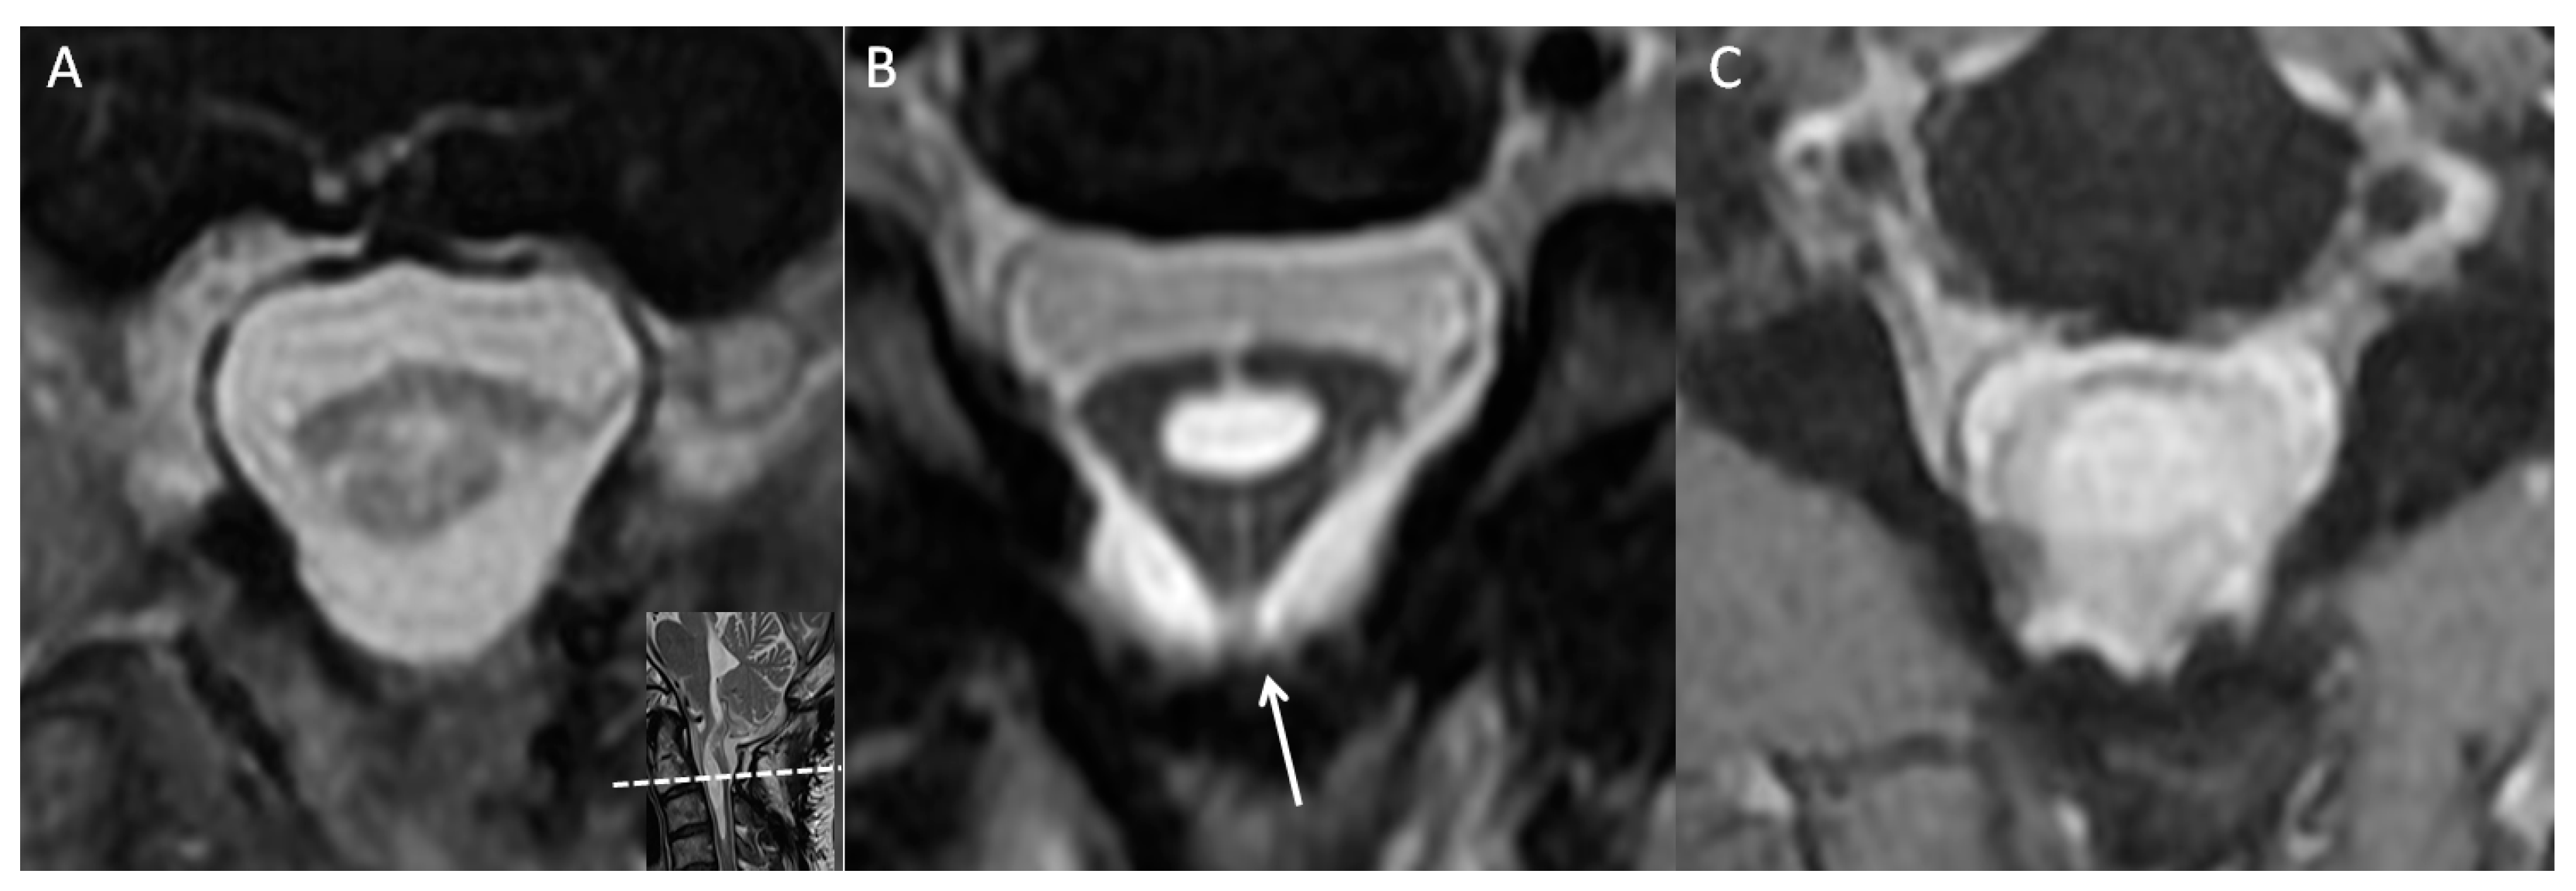

During a review of the patient’s cervical MRI series from previous years, a notable finding was made at the C2 level; that is, a thick arachnoid band was discovered to be attached to the spinal cord and the dural sac, causing the cord to take on a triangular shape in the axial view. This characteristic change in cord shape was termed the “delta cord” sign (Figure 2). Over time, progression of the syrinx from the C2 level to the C4 level was observed. After consideration of potential factors that could contribute to recurrent syringomyelia, postoperative adhesive arachnoiditis was suspected.

Figure 2.

Axial view of the C2 level at multiple time points. (A) Three months after the first surgery. (B) After 1 year, a thick arachnoid band (white arrow) had attached to the posterior aspect of the thecal sac, giving the cord a triangular shape, that is, the “delta cord” sign. Syrinx progression was observed from that point onward. (C) The spinal cord had attached to the thecal sac, and syrinx progression and cord edematous change were observed.